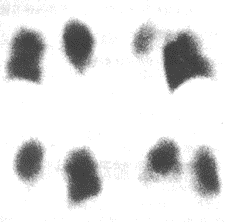

(5)X線胸片示有充血性肺不張或肺梗死,多在12~36h內出現。